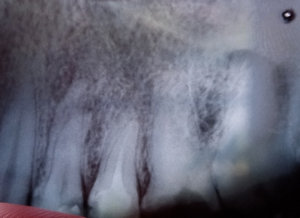

Очень сложно определить, но все Ваши симптомы говорят и свищевом выходе. То есть, на верхушках зуба имеется воспалительный процесс.

Необходимо обратиться к врачу, сделать рентген-снимки и выявить точную причину.